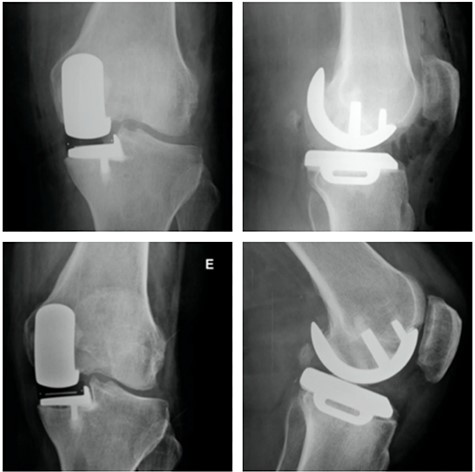

Top: anterior (left) and lateral view (right) X-ray images of the immediate postoperative period (medial UKA); Bottom: anterior (left) and lateral view (right) X-ray images of the same patient with 5 months of follow-up with tibial component loosening.